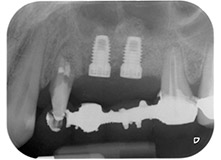

motor de implantes Implantmed

Fig. 8: El siguiente paso fue la preparación rotativa del lecho del implante cerca de la base del seno maxilar en la posición 25, que se realizó con el nuevo motor de implantes Implantmed.

En el siguiente paso, los lechos del implante se prepararon en las posiciones 25 y 26 con instrumentos rotatorios, utilizando un contra-ángulo con un coeficiente de transmisión de 20:1 (WS-75 L, W&H), junto con el nuevo potente motor de implantes Implantmed de W&H (figuras 8 y 19).

A continuación, los implantes (Restore, Keystone Dental, 3,75 mm de diámetro, 8,0 mm de longitud) se colocaron con el motor de implantes (figuras 11 y 12).

listos para los tornillos de cubierta

Fig. 12: Los dos implantes están colocados y listos para los tornillos de cubierta.

radiografía posoperatoria

Fig. 16: La radiografía posoperatoria muestra ambos implantes en sus posiciones correctas, con material sustituto óseo alrededor de los ápices procedente de la elevación interna del seno. También hay material visible alrededor de las raíces de la pieza 24 procedente del procedimiento de GTR.